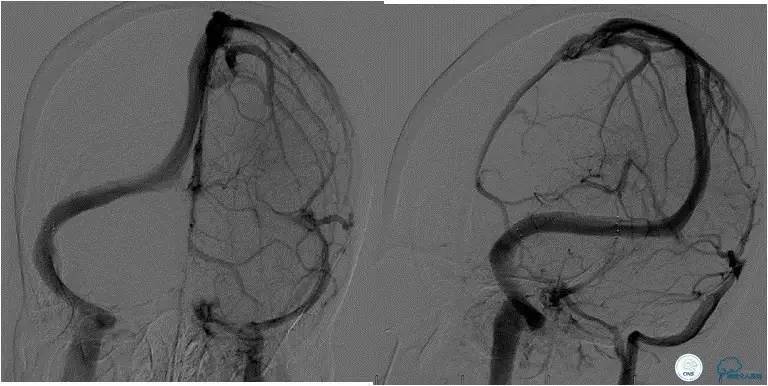

随访经过:3月后患者眼底检查双眼视盘水肿明显消退(图6),视力改善:右眼1.0,左眼0.4;8月后患者入院行脑血管造影(DSA)显示右侧横窦-乙状窦交界处支架通畅,未见再狭窄(图7)。

图7:术后8月随访患者,脑动脉造影显示右侧横窦-乙状窦交界处未见狭窄,支架内通畅良好,未见血栓形成和内膜增生。